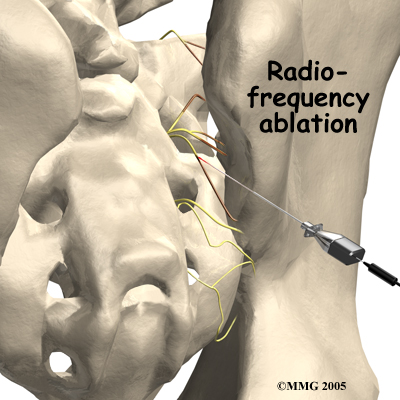

Radiofrequency Ablation

Another procedure that has been somewhat successful is called radiofrequency ablation. After a diagnostic injection has confirmed that the pain is coming from the SI joint, the small nerves that provide sensation to the joint can be "burned" with a special needle called a radiofrequency probe. In theory, this destroys any sensation coming from the joint, making the joint essentially numb. This procedure is not always successful. It is temporary but can last for up to two years. It can be repeated if needed.